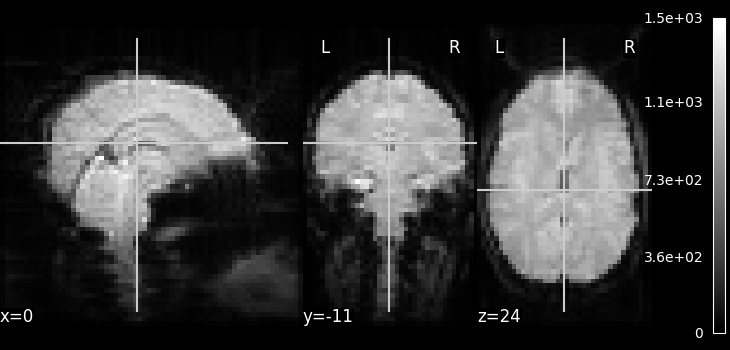

Visualizing the fMRI volume¶

One way to visualize a fMRI volume is

using plot_epi.

We will visualize the previously fetched fMRI

data from Haxby dataset.

Because fMRI data are 4D

(they consist of many 3D EPI images),

we cannot plot them directly using plot_epi

(which accepts just 3D input).

Here we are using mean_img to

extract a single 3D EPI image from the fMRI data.